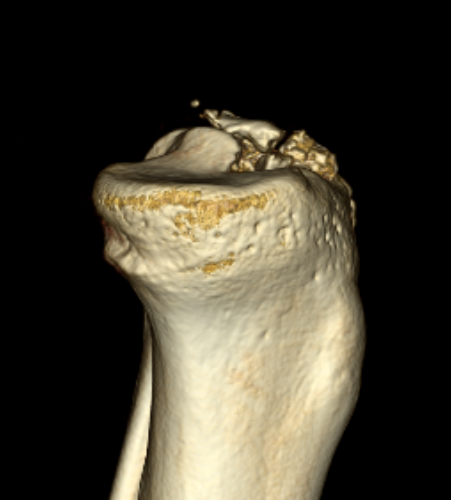

CT

Can help classify and thus guide treatment

Type II Type III

Type IV